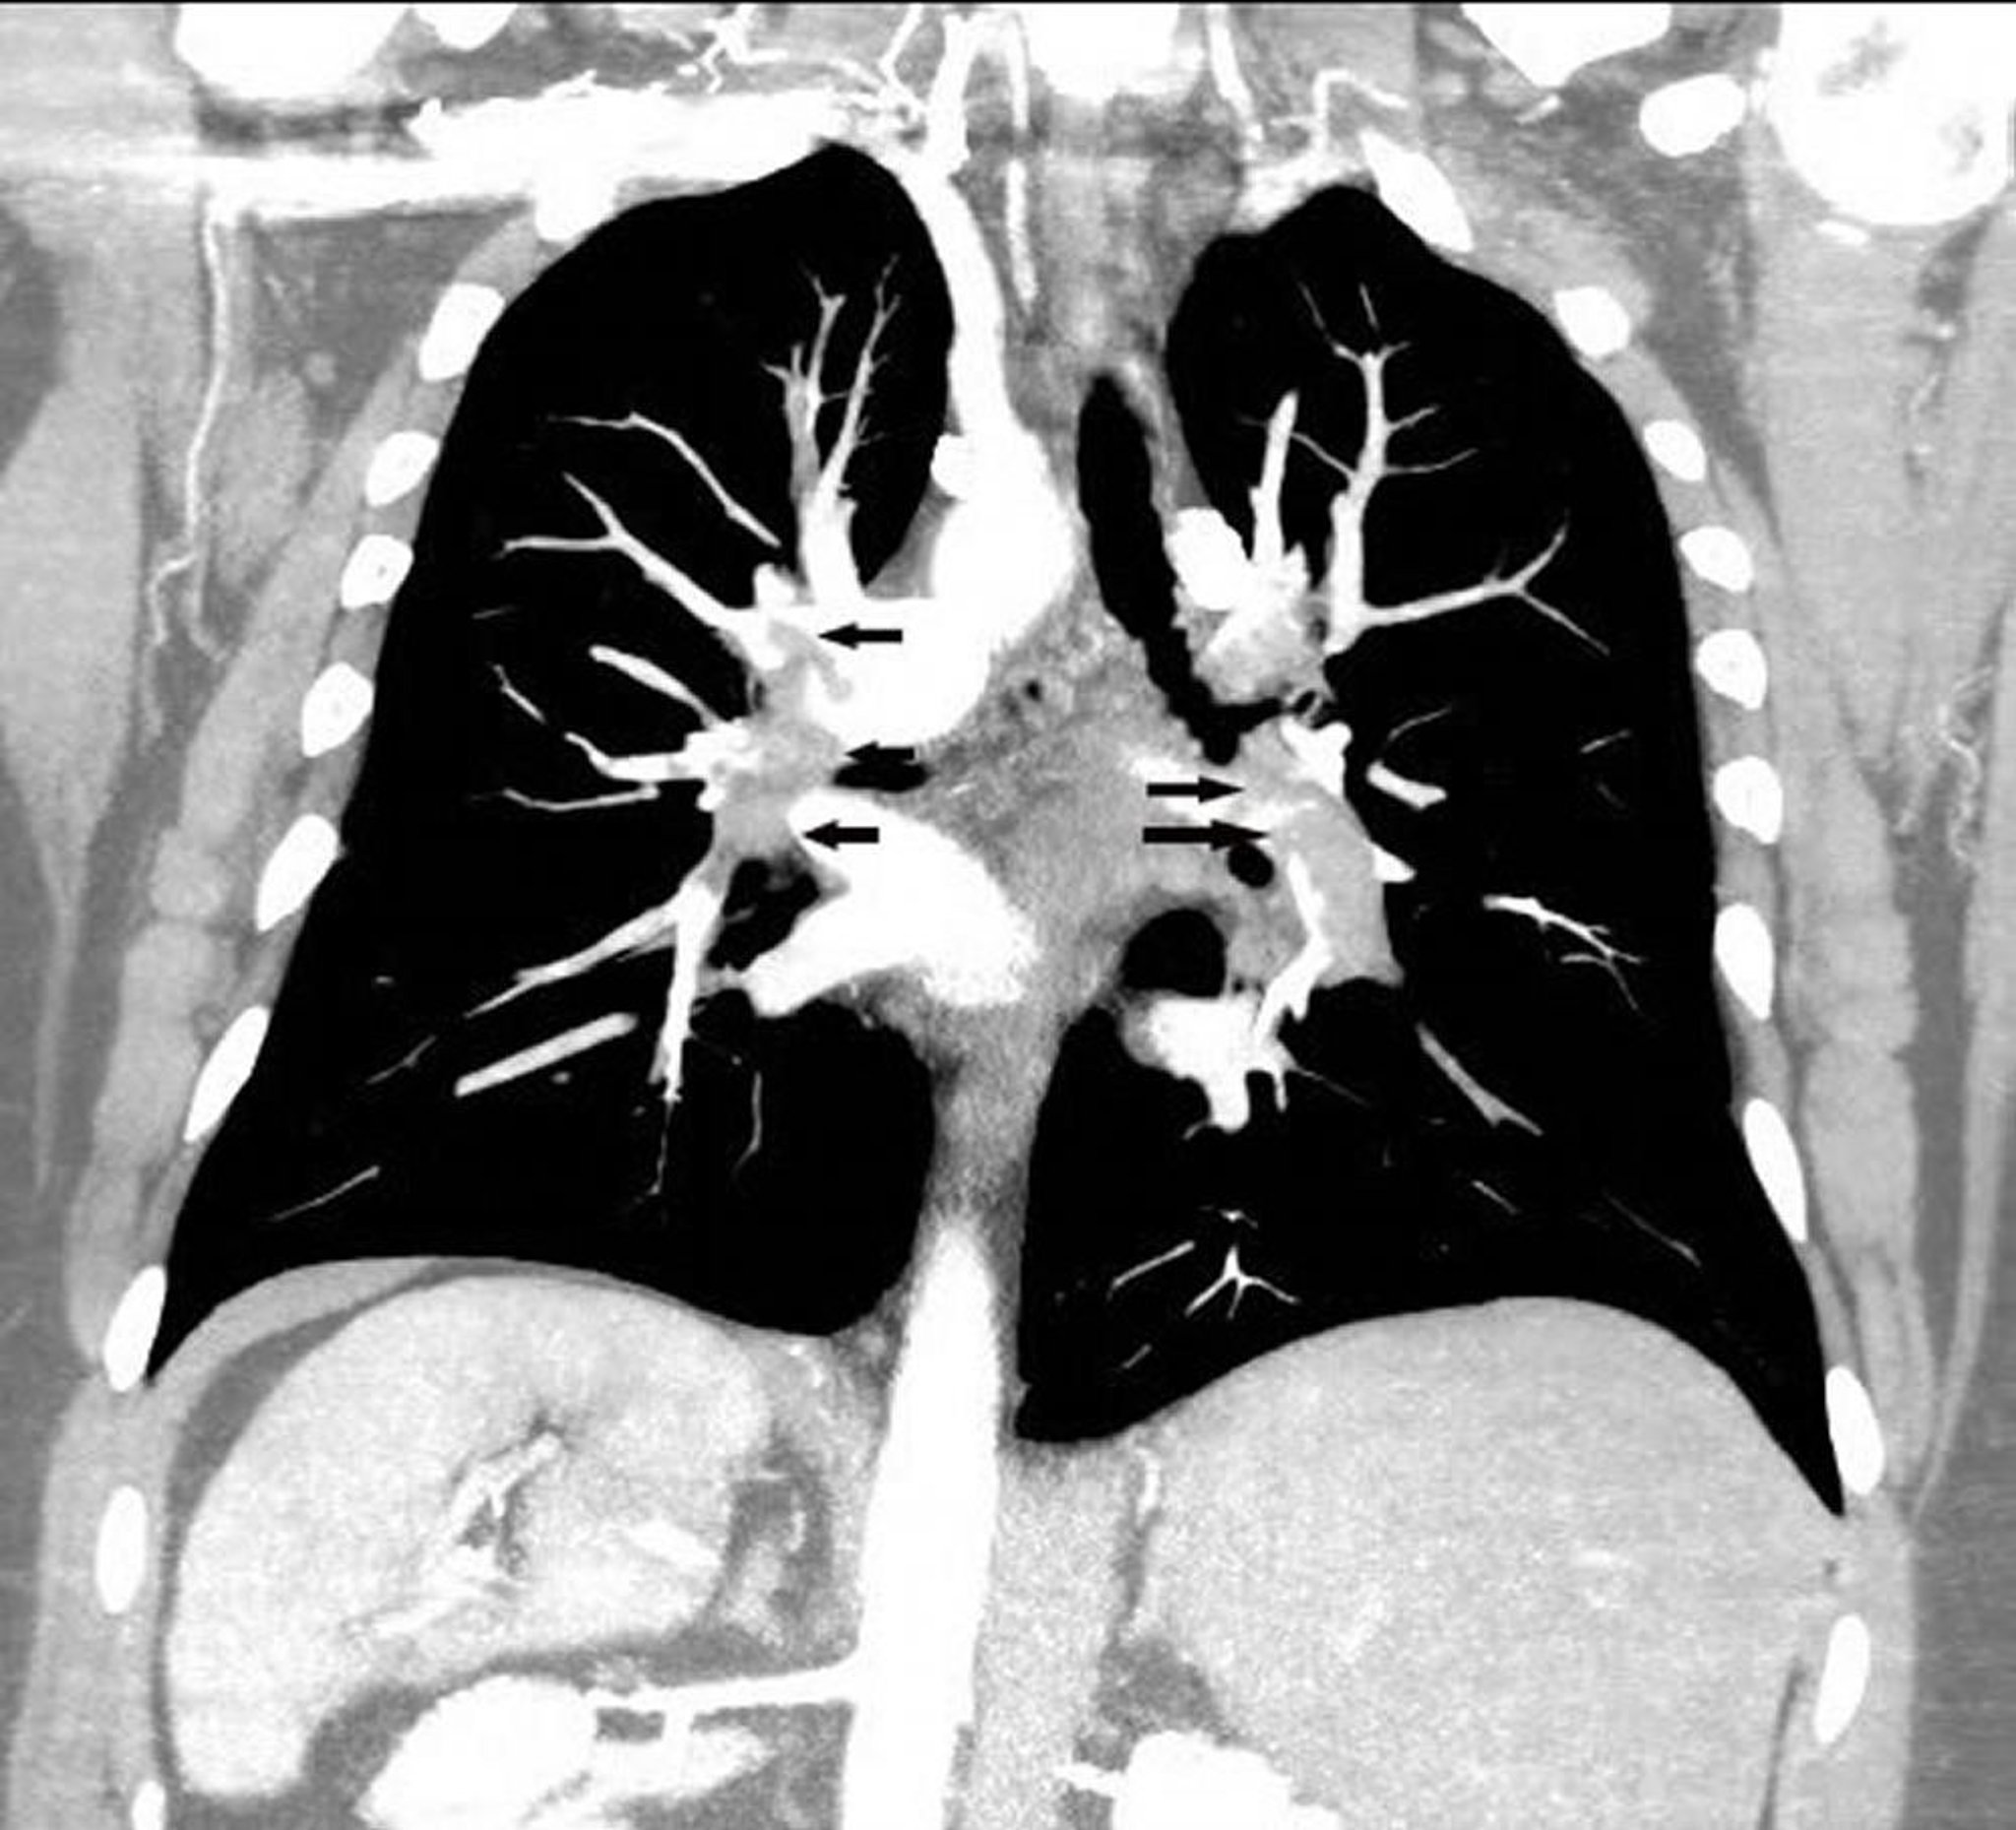

Angiografía pulmonar por TC de reconstrucción coronal

La angiotomografía pulmonar con reconstrucción coronal muestra una embolia pulmonar extensa en ambas arterias pulmonares (flechas).

Image courtesy of Hakan Ilaslan, MD.